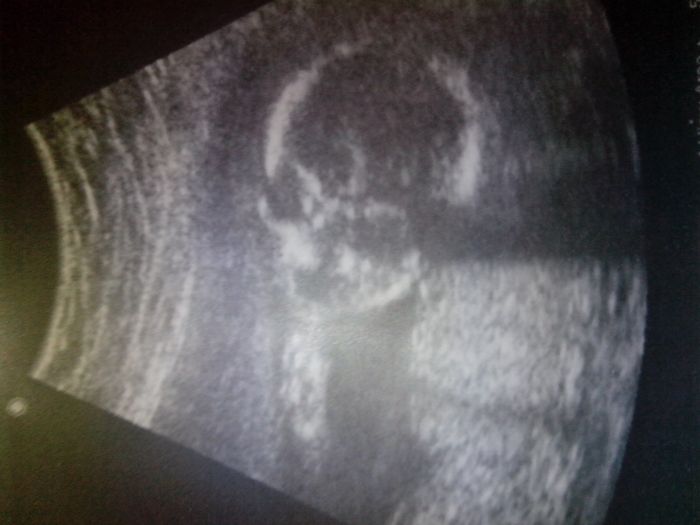

Jo a tady je fotka ze vcerejska ;)